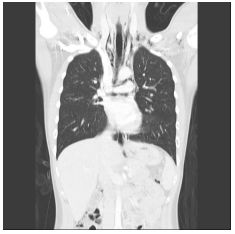

1. A 39-year-old man had this chest X-ray on his health exam. No any clinical symptoms.